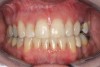

Figure 2a  Corticotomy SFOT. The patient presented with unesthetic anterior bridgework that was placed at age 14 to compensate for congenitally missing Nos. 7 and 10.

Figure 2a

Figure 2d  Prerestorative orthodontics was completed in 5 months. Final result 3 years, 4 months after completion.

Figure 2d

Figure 2e  Teeth Nos. 5 and 12 were converted to Nos. 6 and 11, and Nos. 6 and 11 were converted to Nos. 7 and 10. Nos. 4 and 13 were enlarged. Note stability and absence of orthodontic relapse. Before-and-after smiles.

Figure 2e

Figure 2f  Teeth Nos. 5 and 12 were converted to Nos. 6 and 11, and Nos. 6 and 11 were converted to Nos. 7 and 10. Nos. 4 and 13 were enlarged. Note stability and absence of orthodontic relapse. Before-and-after smiles.

Figure 2f